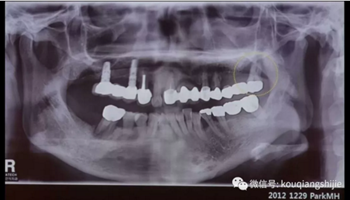

這個患者在2012年的時候#17已經(jīng)是需要拔除的情況,但是因為患者要求保留,所以我們進行保守治療

4年后患者再次就診,要求拔出

這時候我們可以看到患牙周圍已經(jīng)沒有任何骨壁。

我們可以看到#17,18的牙周炎非常嚴重

從CT上我們可以看到骨破壞非常嚴重

拔牙后也將拔牙窩內(nèi)的黏膜提拉上來

十周之后我們可以看到黏膜組織沒有出現(xiàn)凹陷

翻瓣之后可以看到形成的充足的骨量